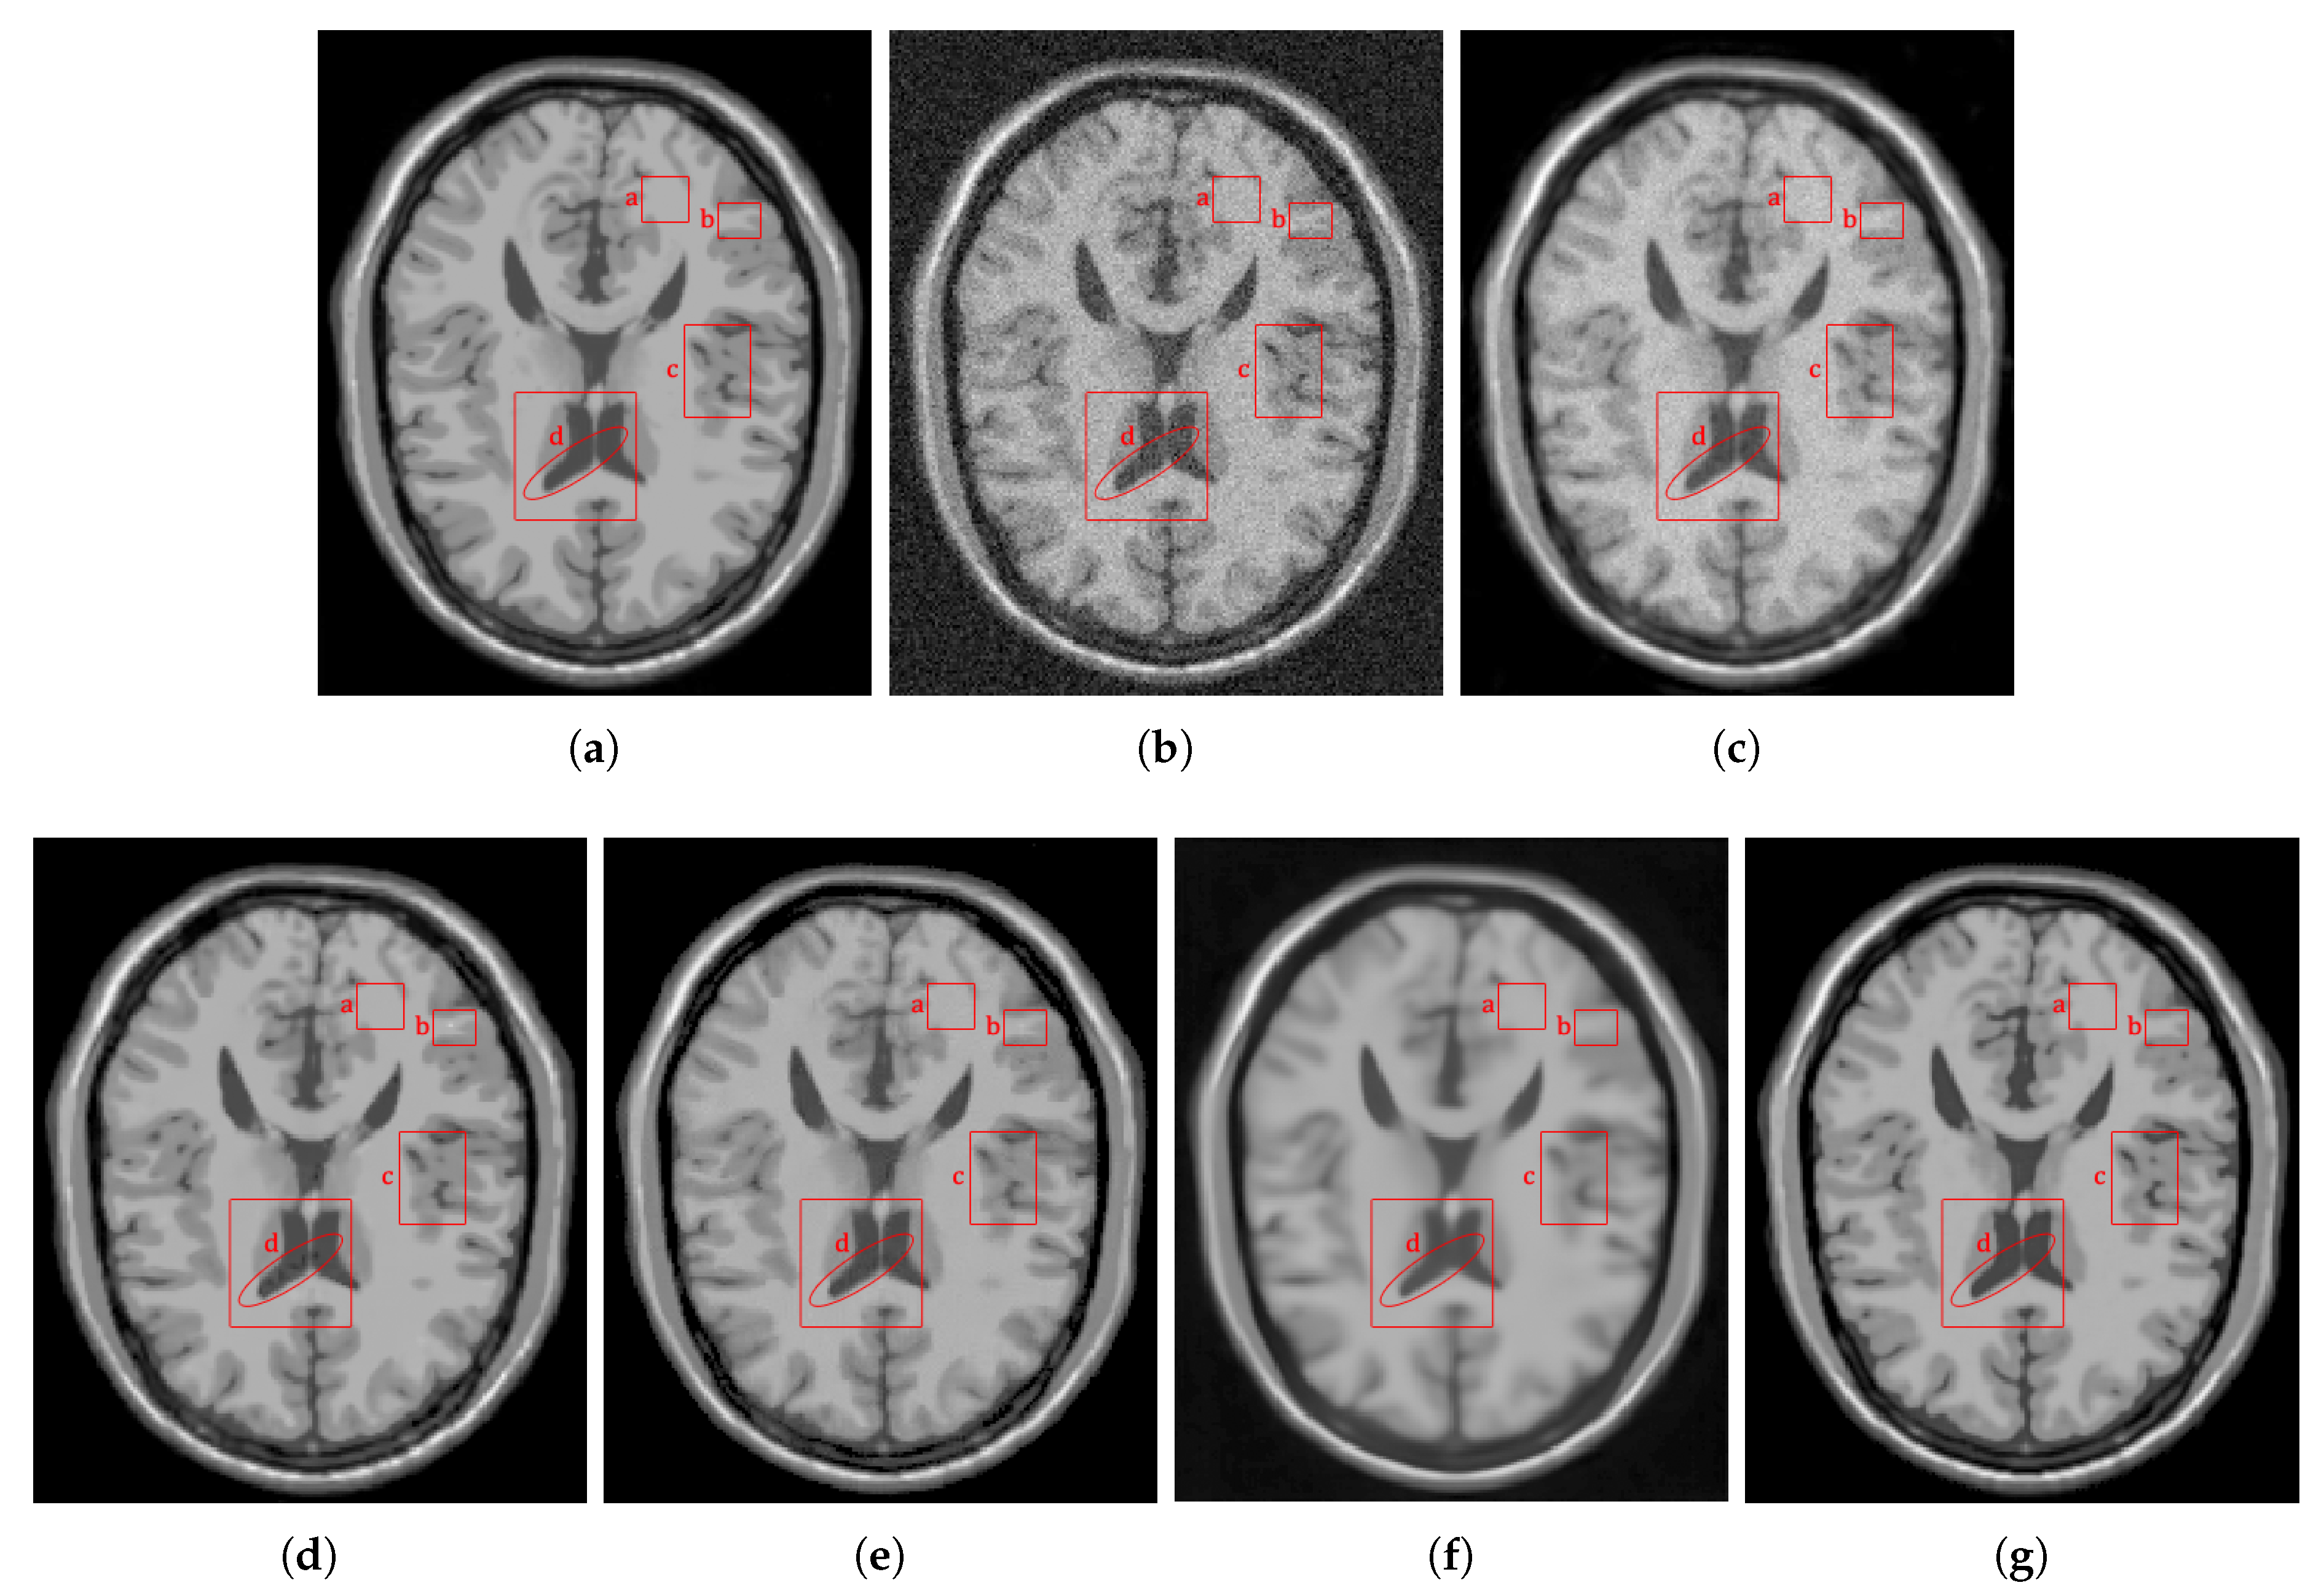

4.2.1. Synthetic Data

4.2.2. Real Data